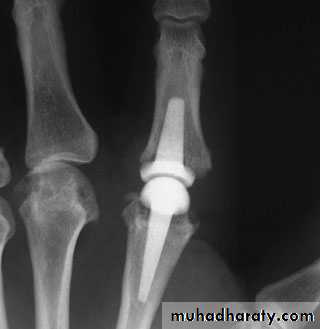

OSTEOARTHRITIS

PROXIMAL INTERPHALANGEAL JOINTS:

(Bouchard’s nodes).Strongly associated with osteoarthritis elsewhere in the body (polyarticular OA).

The joints are swollen and tend to deviate ulnarwards due to mechanical pressure in daily activities.

Treatment : is usually non-operative. If the joint is very painful or unstable then surgery is considered. Fusion restores reliable, pain-free pinch in the index and middle finger PIP joints; fusion of the ring and little fingers compromises grip and so joint replacement is usually preferable.

Carpo-metacarpal joint of the thumb:

Osteoarthritis of the trapezio-metacarpal joint is common in postmenopausal women.Heberden’s nodes of the finger joints,

bilateral and part of a generalized osteoarthritis.